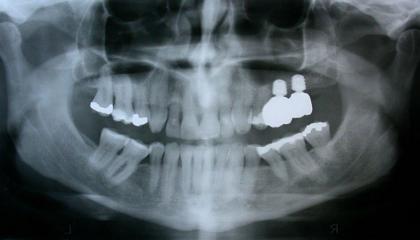

Before